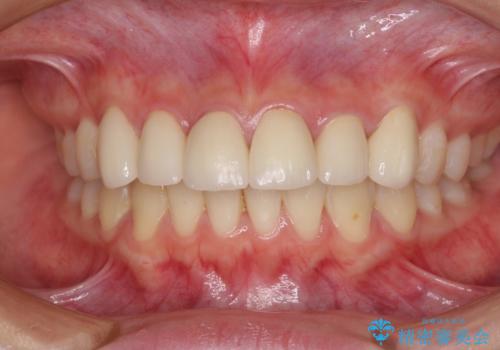

普段は海外在住であり、出産のための一時帰国を利用して短期集中治療を行いました。

自身の出産で大変な時期にもかかわらず、スケジュール通りに通院いただき、望まれたとおりの口元に仕上げることができました。